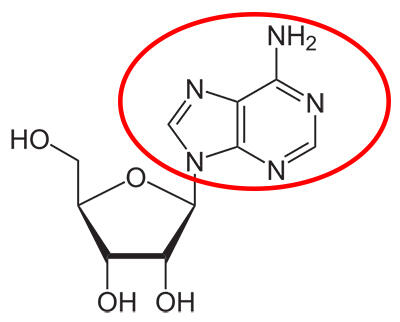

1. Persamaan reaksi kafein itu akan terlihat seperti ini

Bentuk kafein mirip dengan molekul penting yang disebut "adenosin" yang mengatur fungsi otak (gambar dibawah). Kafein "meniru" adenosine dan mengikat target yang sama di otak

Bentuk kafein mirip dengan molekul penting yang disebut "adenosin" yang mengatur fungsi otak (gambar dibawah). Kafein "meniru" adenosine dan mengikat target yang sama di otak

5. Kafein bekerja dengan menghalangi efek dari regulator alami otak, yaitu adenosin

Pada siang hari, otak Anda secara alami membangun tingkat atas adenosin. Ketika mereka mencapai konsentrasi ambang batas, mereka mengikat reseptor khusus yang bereaksi dengan petunjuk mulai menembak untuk membuat tubuh Anda mengantuk.

Ingat bagaimana kafein memiliki bentuk mirip dengan adenosin? Ini berarti bahwa ia dapat mengikat reseptor yang sama, menghalangi efek alami adenosin. Hal ini memungkinkan stimulan otak untuk bekerja tanpa hambatan, membuat Anda terjaga dan waspada.

Pada siang hari, otak Anda secara alami membangun tingkat atas adenosin. Ketika mereka mencapai konsentrasi ambang batas, mereka mengikat reseptor khusus yang bereaksi dengan petunjuk mulai menembak untuk membuat tubuh Anda mengantuk.

Ingat bagaimana kafein memiliki bentuk mirip dengan adenosin? Ini berarti bahwa ia dapat mengikat reseptor yang sama, menghalangi efek alami adenosin. Hal ini memungkinkan stimulan otak untuk bekerja tanpa hambatan, membuat Anda terjaga dan waspada.